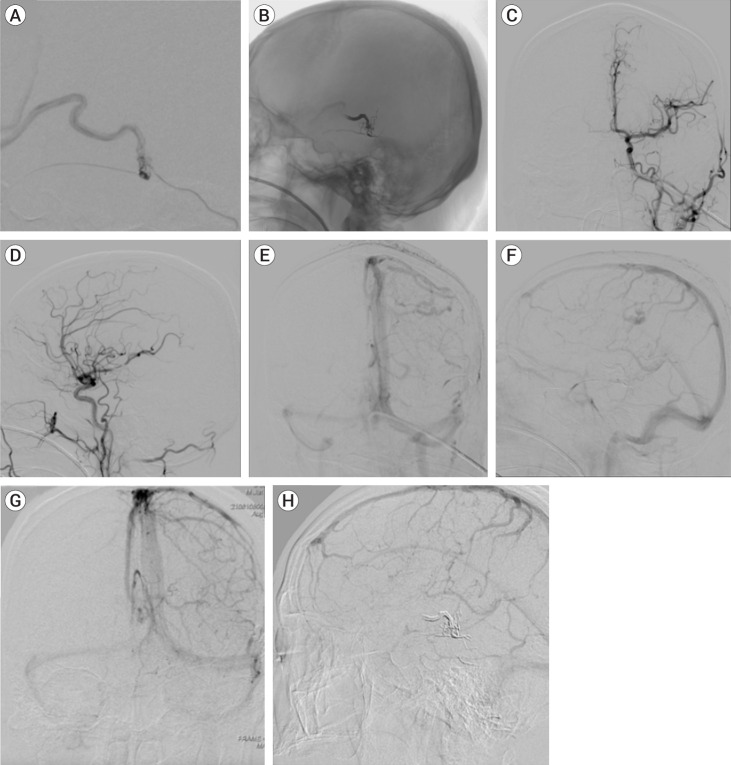

凸面硬脑膜动静脉瘘(dAVF)与高级别硬脑膜动静脉瘘有关,通常具有侵袭性临床表现。准确诊断和了解发病机制对于成功治疗而不出现并发症非常重要。我们报告了一例伴有 Sylvian-Labbé 侧支模式的 dAVF 病例,该模式涉及胚胎发育,被认为与硬膜外动静脉瘘的血管结构和发病机制有关。因此,一名 60 岁的男性患者在没有外伤史的情况下突然出现癫痫发作。磁共振成像(MRI)显示左侧前脑回皮质出血。数字减影血管造影(DSA)显示,凸面硬脑膜动静脉瘘(dAVF)累及一条疑似拉贝静脉的静脉,引流管与大脑中上静脉(SMCV)吻合,形成静脉曲张。经动脉栓塞术(TAE)成功治疗后,dAVF得以消除,且无神经功能障碍。该病例强调了凸面静脉瘘与胚胎发育和弧形静脉引流路径之间的复杂关系,其中异常可能是后天形成的,也可能是由一条看似拉贝静脉的静脉压力升高引起的。了解胚胎学基础有助于加深对后天病理的理解。

Convexity dural arteriovenous fistula (dAVF) is associated with high-grade dAVF and is usually presented with aggressive clinical presentation. Precise diagnosis and understanding the pathogenesis are important to achieving successful treatment without complications. We report a case of dAVF with Sylvian-Labbé collateral pattern, concerning embryological development that was thought to be involved in the vascular architecture and pathogenesis of dural AVF. Thus, a 60-year-old man was presented with sudden onset of seizure with no history of trauma. Magnetic Resonance Imaging (MRI) showed cortical hemorrhage in the left precentral gyrus. Digital subtraction angiography (DSA) showed the convexity dural arteriovenous fistula (dAVF) involving a vein that appeared to be the vein of Labbé, the drainer was anastomosed with superior middle cerebral vein (SMCV) and formed the varix. With the successful treatment with trans-arterial embolization (TAE), obliteration of dAVF was achieved with no neurological deficits. This case highlights convexity dAVF with the complex relationship between embryological development and the arcade of venous drainage route, wherein the anomaly might be acquired and caused by elevated venous pressure in a vein that appeared to be the vein of Labbé. Gaining knowledge of the embryological basis may aid in a deeper understanding of acquired pathologies.